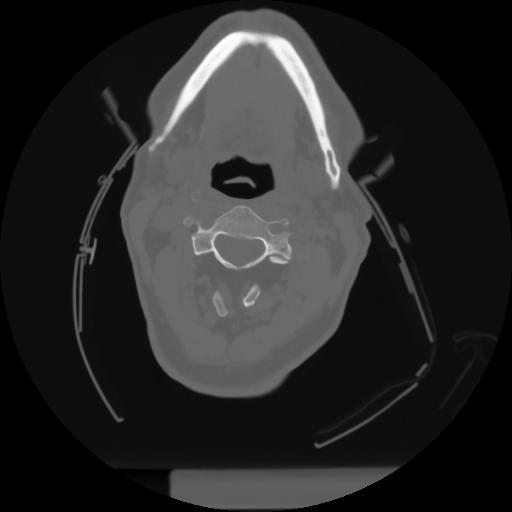

10 P.BLANDAS,,Axial,2.0,P.BLANDAS,,